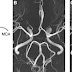

The network of arteries supplying blood flow to the brain is more likely to be incomplete in people who suffer migraine, a new study by researchers in the Perelman School of Medicine at the University of Pennsylvania reports. Variations in arterial anatomy lead to asymmetries in cerebral blood flow that might contribute to the process triggering migraines.The arterial supply of blood to the brain is protected by a series of connections between the major arteries, termed the "circle of Willis" after the English physician who first described it in the 17th century. People with migraine, particularly migraine with aura, are more likely to be missing components of the circle of Willis.

In a study of 170 people from three groups -- a control group with no headaches, those who had migraine with aura, and those who had migraine without aura -- the team found that an incomplete circle of Willis was more common in people with migraine with aura (73 percent) and migraine without aura (67 percent), compared to a headache-free control group (51 percent). The team used magnetic resonance angiography to examine blood vessel structure and a noninvasive magnetic resonance imaging method pioneered at the University of Pennsylvania, called Arterial spin labeling (ASL), to measure changes in cerebral blood flow.

"Abnormalities in both the circle of Willis and blood flow were most prominent in the back of the brain, where the visual cortex is located. This may help explain why the most common migraine auras consist of visual symptoms such as seeing distortions, spots, or wavy lines," said the study's senior author, John Detre, MD, Professor of Neurology and Radiology.